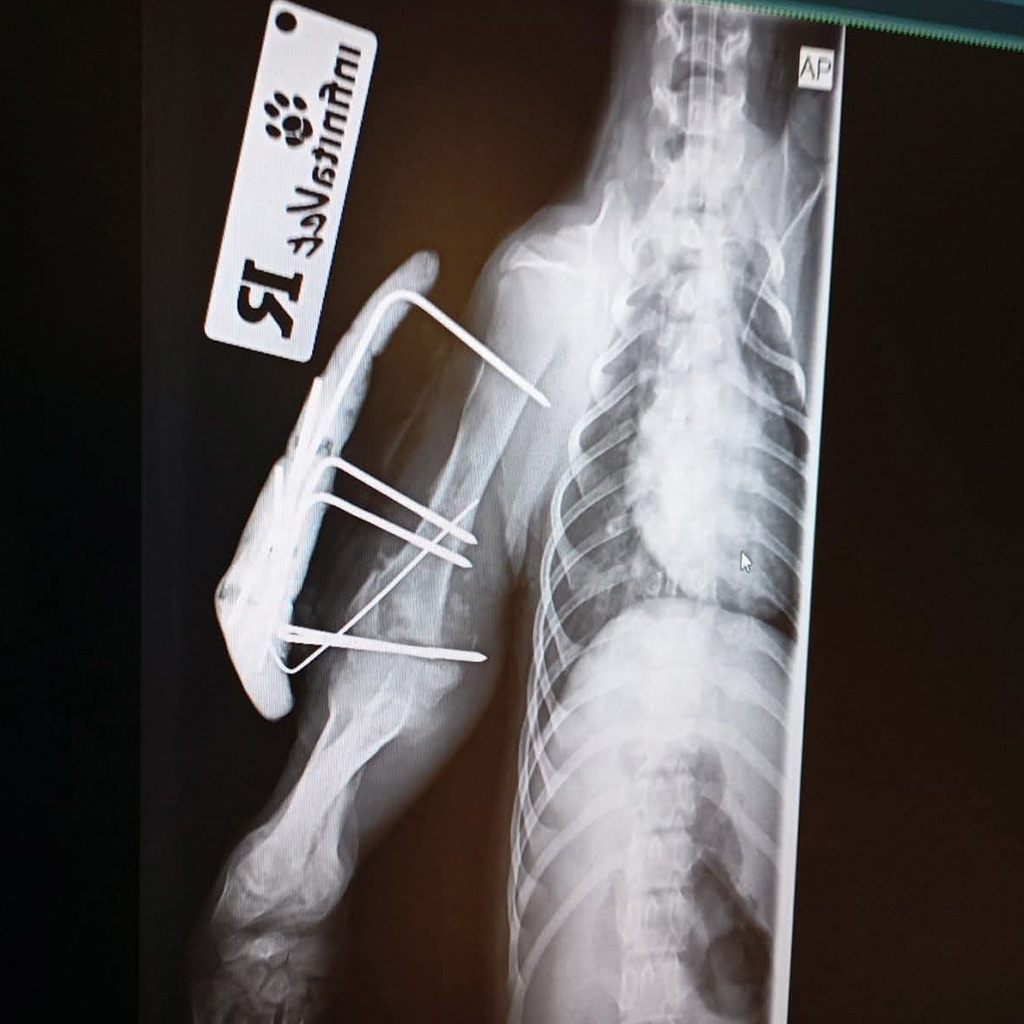

Zum Glück wurde Luca gefunden und sofort in eine Tierklinik gebracht. Dort folgte die erschütternde Diagnose: Ein Vorderbein und ein Hinterbein sind gebrochen. Die Röntgenbilder bestätigten das ganze Ausmaß ihrer Verletzungen.

Die Fraktur am Hinterbein kann ohne Operation ausheilen, hier ist strenge Schonung ausreichend.

Doch das Vorderbein ist so schwer verletzt, dass eine Operation dringend notwendig ist. Um eine stabile und dauerhafte Heilung zu ermöglichen, muss ein Metallimplantat eingesetzt werden. Nur so hat Luca die Chance, später wieder schmerzfrei zu laufen und ein normales Hundeleben zu führen.

Was ursprünglich nicht absehbar war: Sowohl ihr Vorderbein als auch ihr Hinterbein mussten operiert werden.

Das rechte Hinterbein wurde mit einer Platte stabilisiert und ist aktuell noch in einem schützenden Verband. Hier geht es zu Luca’s Video.

Ihr Vorderbein konnte nur mithilfe eines Fixateur externe (Fix Ex) versorgt werden – eine aufwendige, aber notwendige Maßnahme, um ihr überhaupt eine Chance auf eine schmerzfreie Zukunft zu geben. Dieser Fix Ex wird nach einiger Zeit wieder entfernt.